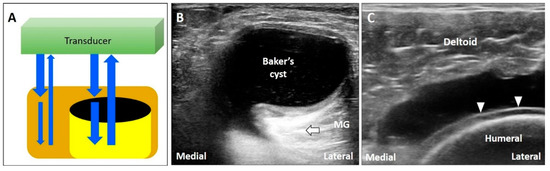

3.5. Mirror Image Artifact

3.5.1. Physics

3.5.2. Clinical Examples